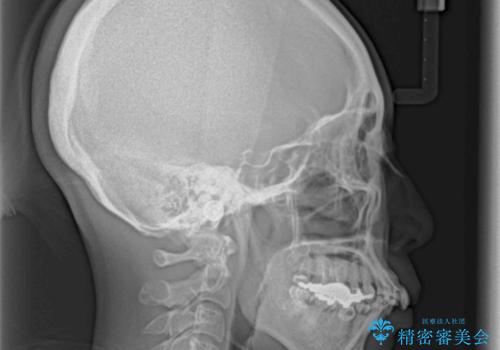

- 歯列全体が内側に倒れ込んでいることと、口元の突出感を気にして来院された患者様です。

上下ともに歯列が狭窄しており、前方に突出している状態でした。

歯が重なるような叢生も認められたため、上下左右の第一小臼歯4本を抜歯して、口元が引っ込むように治療を行うこととしました。